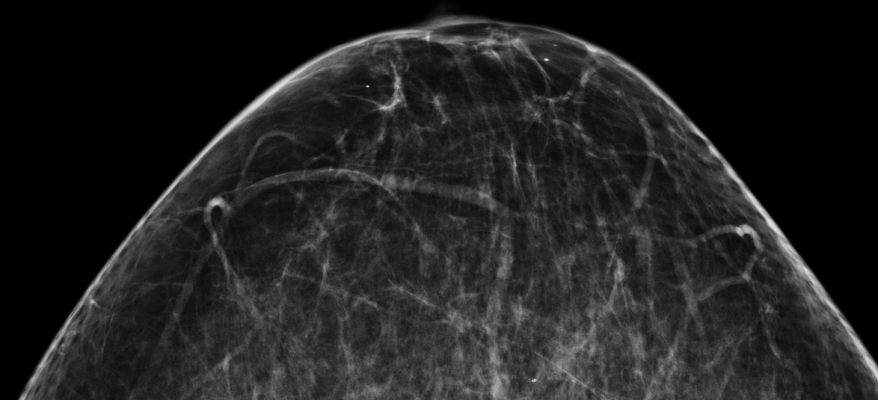

- Breast Cancer Screening;